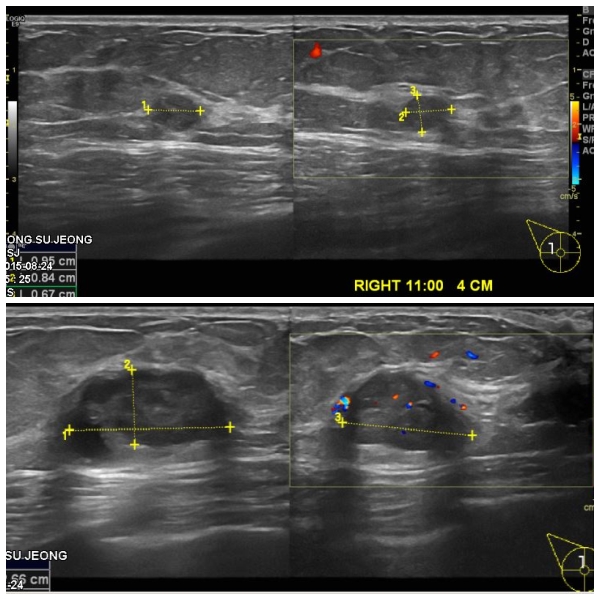

이틀전 우연히 우측유방 멍우리 발견하여 내원하신 70대 여자분으로 본원에서

우측유방 12시방향 1cm떨어진곳과,11시방향 4cm 떨어진 곳에 조직검사 시행한 후

우측유방 유두상피내암 진단되었습니다.